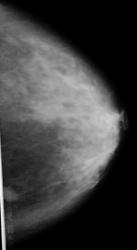

Пациентка при обращении в поликлиннику предъявляла жалобы на периодические боли в левой молочной железе. При исследовании больной, в левой молочной железе было обнаружено образование размером 8мм в верхне-внутреннем пространстве.

На представленной маммограмме в верхнем внутреннем квадранте молочной железы определяется тень средней интенсивности, довольно однородной структуры в виде "узлового образования" с не весьма ровными и четкими контурами. Конечно, если-бы контуры были ровные, четкие, то тогда все симпатии в сторону фиброаденомы. Но стоит повториться по поводу контуров, да и две подчеркнуто усиленные линейные тени навевают сомнения. Я-бы, не вдаваясь в подробности, отправил-бы пациентку к маммологу-онкологу. Все одно биопсия в данном случае должна быть. Так себя вполне может вести "маленький рачок", даже с учетом того, что это не верхний наружный квадрант.

Игорь Артурович, расскажите о технической стороне дела: какой аппарат, кассета-пленка, фотообработка? Мне кажется есть погрешности в укладке-компрессии железы, нет тени большой грудной мышцы и задний край образования срезан Хмурый вот я и хочу понять, следствие ли это конструктивных особенностей аппарата или методики?

Выполнением снимка занимался лаборант, который занимается там недавно. Я к этому аппарату доступа не имею, но аппарат старого цифрового типа. А суть исследования была такова: 3 года назад был обнаружен узел хирурургом при пальпации в  нижнем наружном квадрантелевой молочной железы. Женщина активно лечилась, но с тех пор больше не обследовалась.